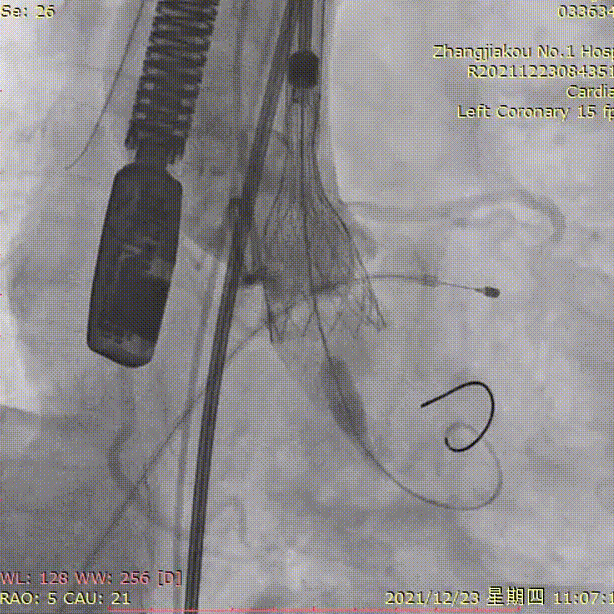

瓣膜释放到工作位

瓣膜脱钩

释放后造影

瓣中瓣植入